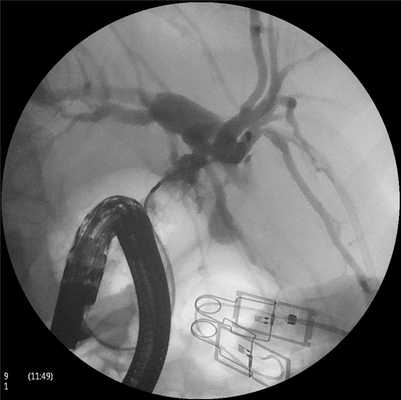

От 23.08. — 11 белок 77,0 г/л, мочевина 10,7 ммоль/л, креатинин 0,14 мкмоль/л, билирубин общий 13,8 мкмоль/л, холестерин 3,3 ммоль/л, калий 4,8 ммоль/л, натрий 153 ммоль/л, железо 7,3 мкмоль/л, АлАТ 16 ед, АсАТ 18 ед, щелочная фосфатаза 338 ед, α-амилаза 152 ед., лейкоциты 10,5·10 9 /л, От 24.08.11: при ЭРПХГ получено изображение протока поджелудочной железы, расширенного на всем протяжении до 4 мм. Создается впечатление, что головка поджелудочной железы увеличена. Выполнена канюляция гепатикохоледоха, последний диаметром от 0,6 мм в терминальном отделе до 1,5 см в проекции общего печеночного протока (ОЖП), содержит не менее 3 дефектов наполнения разнообразной формы и величины. Пузырный проток не контрастирован, желчный пузырь 1,6×1×1,5 см, содержит дефект наполнения, часть которого выступает в просвет ОЖП. Внутрипеченочные протоки умеренно расширены. В направлении 12 ч условного циферблата в режиме коагуляции выполнено рассечение интрамурального отдела ОЖП протяженностью около 1,5 см. Отмечалось кровотечение, которое было остановлено орошением 96% раствором спирта и обкалыванием раствором 0,1% адреналина с аминокапроновой кислотой. От продолжения исследования решено было воздержаться (рис. 1). Рисунок 1. Холедохолитиаз. Камень, частично вышедший из желчного пузыря, в просвет желчного протока. Пузырный проток не контрастирован.

Заключение: синдром Мирицци-2, хронический калькулезный холецистит, множественный холедохолитиаз, атрофический гастродуоденит, хронический панкреатит.